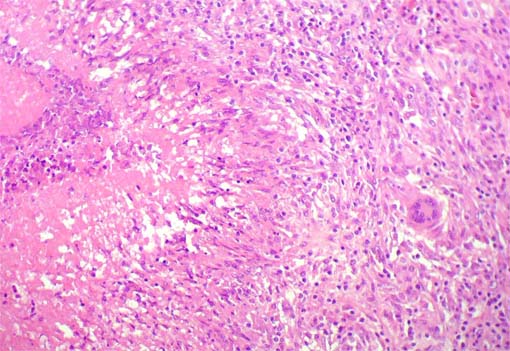

Figura 4.

H&E, X200.